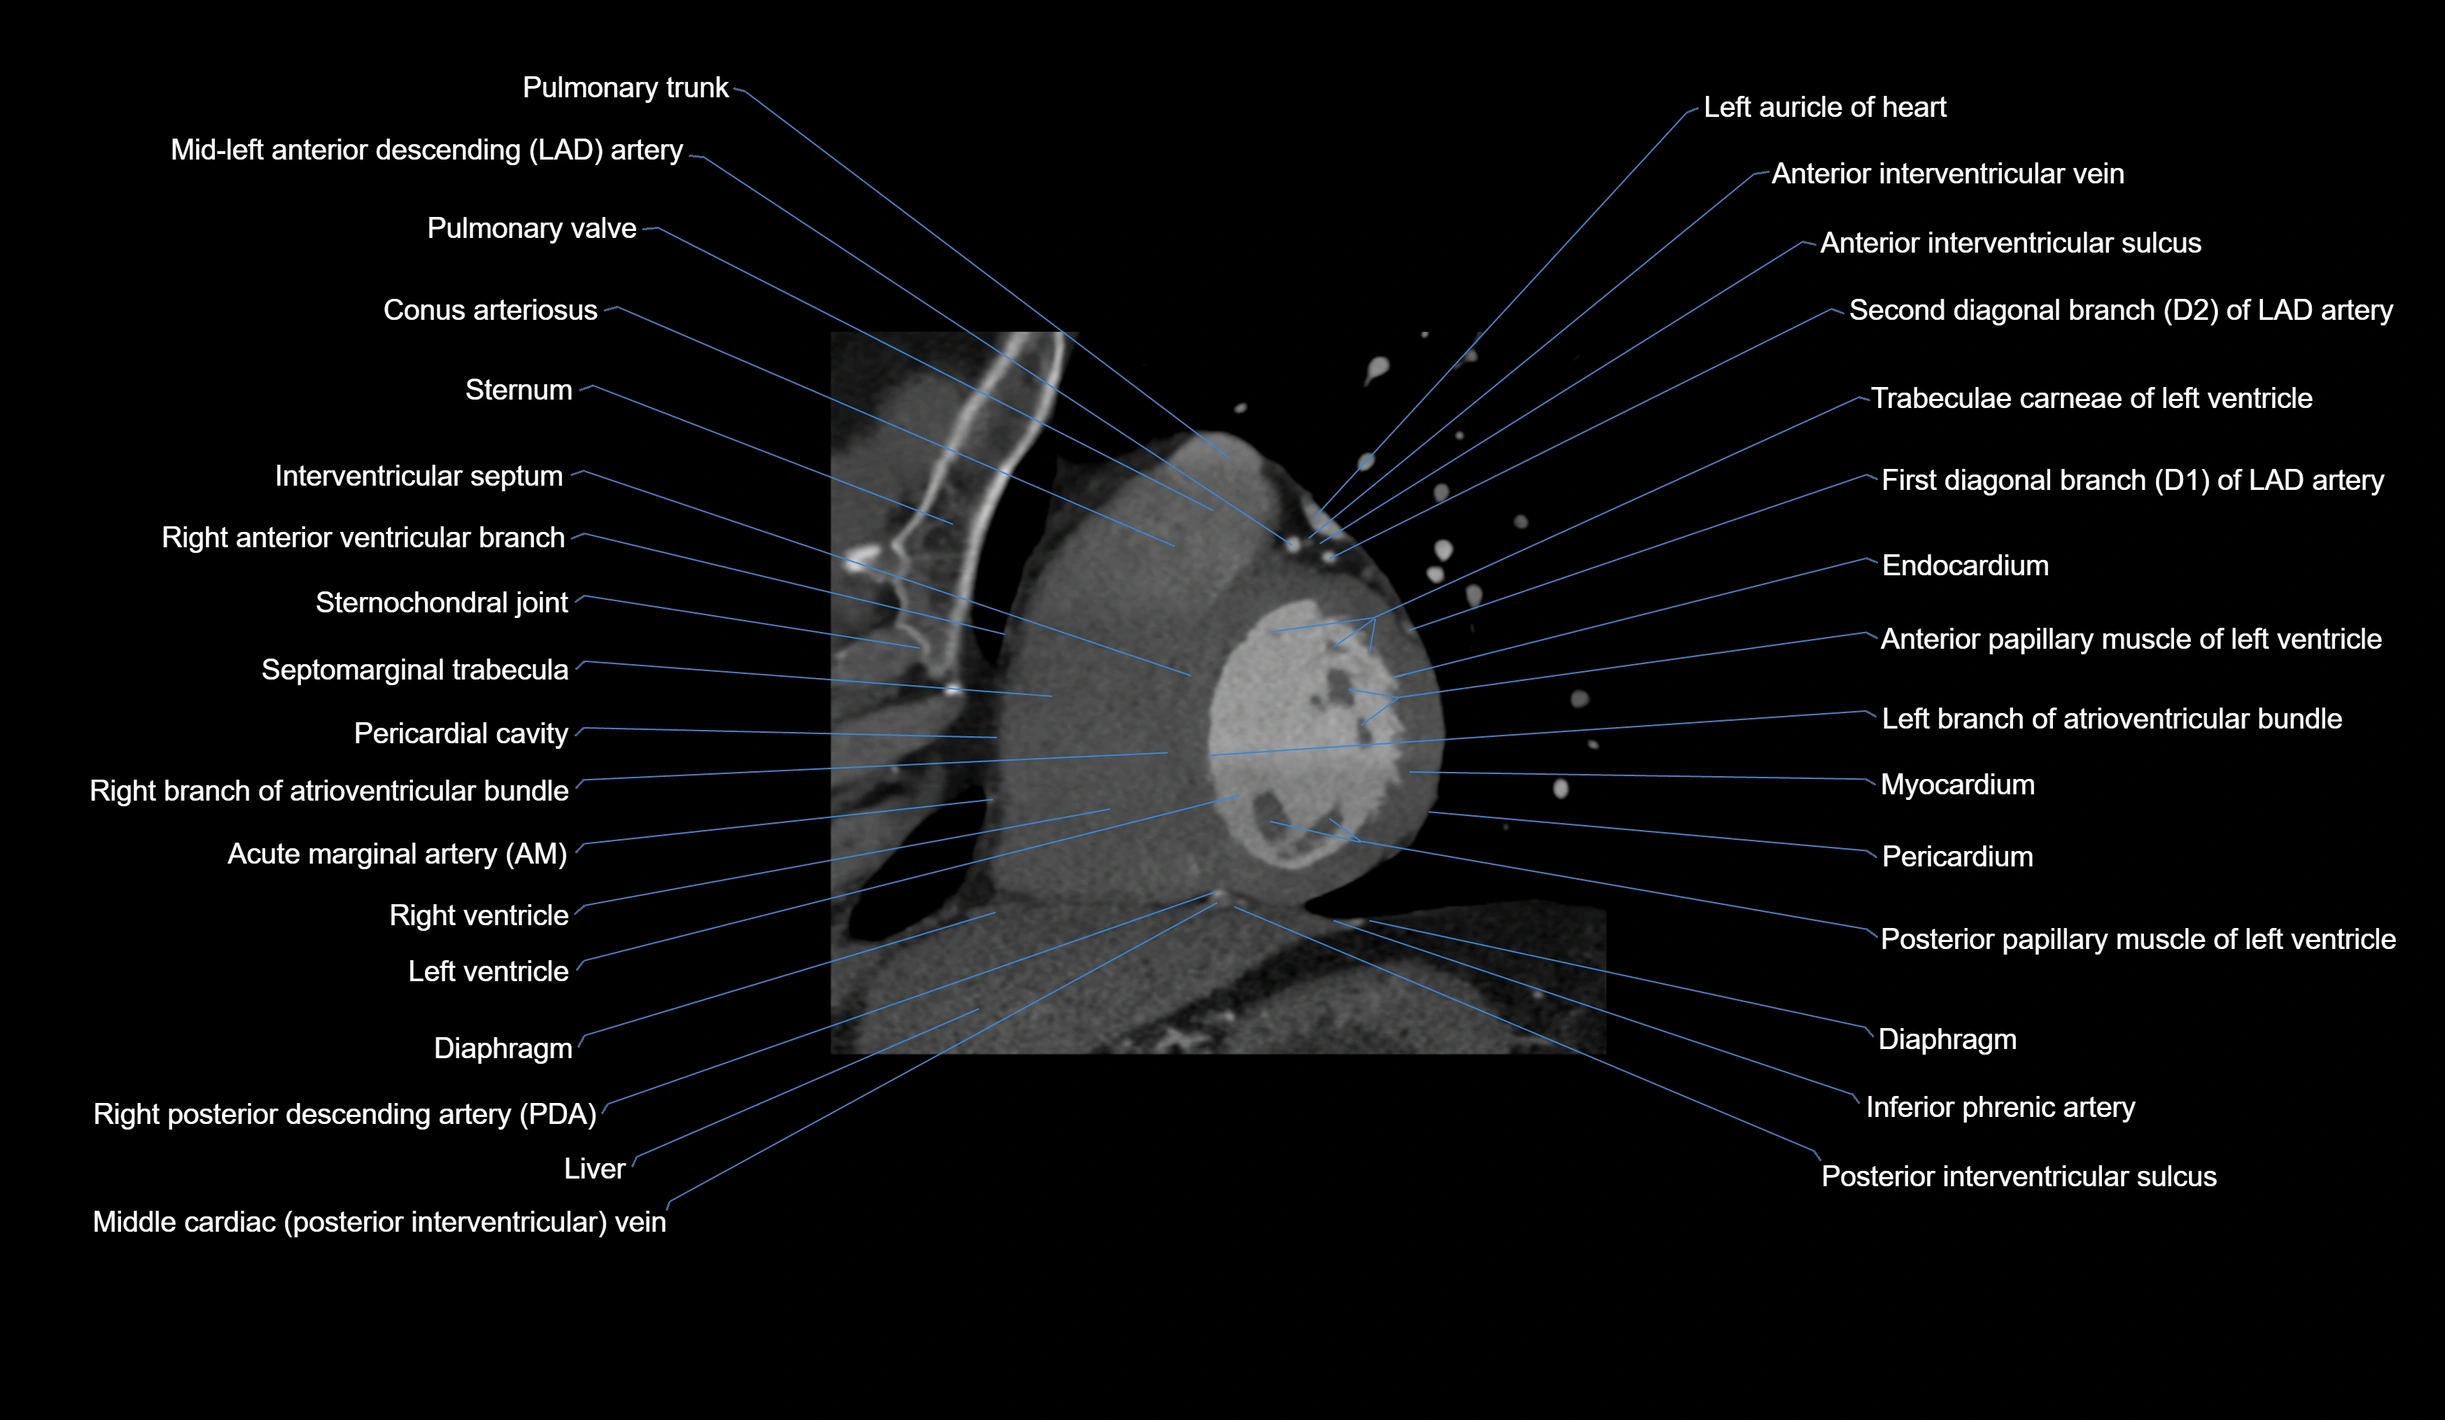

CT Appearance

Non-contrast CT (Calcium Scoring):

-

AM artery visualized for coronary calcium scoring

Calcified plaques appear as hyperdense foci; scored with Agatston method

CT Coronary Angiography (CCTA):

Best non-invasive modality for acute marginal artery visualization

Shows origin, course along the acute margin, and right ventricular branches

Detects stenosis, occlusion, calcified and non-calcified plaques, aneurysm, or anomalous course

Multiplanar reformats and 3D reconstructions help in pre-PCI and surgical planning

Critical for assessing right ventricular infarction risk in RCA disease

MRI image

CT images